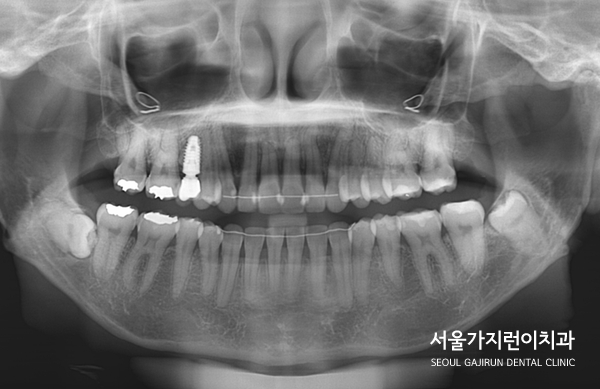

문제는 상악 우측 제1대구치에 임플란트를 식립한 환자라는 점입니다.

임플란트는 교정력이 있어도 이동하지 않으며 이 부분에 힘이 가해질 경우

임플란트의 파손으로 이어질 수 있어 상당한 주의가 필요한데요.

임플란트의 존재와 임플란트 주변의 치아 이동에 제한이 있기 때문에

꼼꼼한 교정플랜이 뒷받침되어야 했습니다.

그래서 상기 환자의 경우 상악 전치의 전돌을 해소하기 위해

미니스크류를 사용한 치아교정이 이루어졌는데요.

설측탄댐방식을 이용해 치아이동에 필요한 힘을 충분히 줄 수 있었습니다.

상기 환자분의 경우 임플란트 치아가 움직이지 않도록 최대한 노력하였으며

다행히도 임플란트 이상 없이 교정력을 유지하면서 치아교정을 마무리할 수 있었습니다.